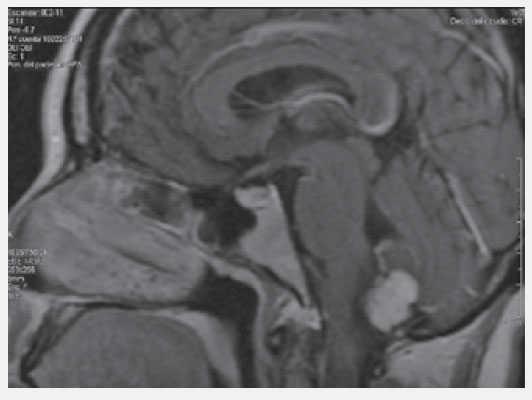

Abdomen globoso, a expensas de panículo adiposo, no adenomegalia, no se palpan masas, dolor a la palpación en epigastrio. Glucosa: 76 mg/dL, Creatinina: 0.87 mg/dL, amilasa y lipasa normales, TC abdomen: Lesiones quísticas de páncreas y ambos riñones. IRM Abdomen: Lesiones quísticas en páncreas y ambos riñones. IRM de cerebro: Hemangioblastoma en cerebelo.

Figura 3. IRM quistes pancreáticos.